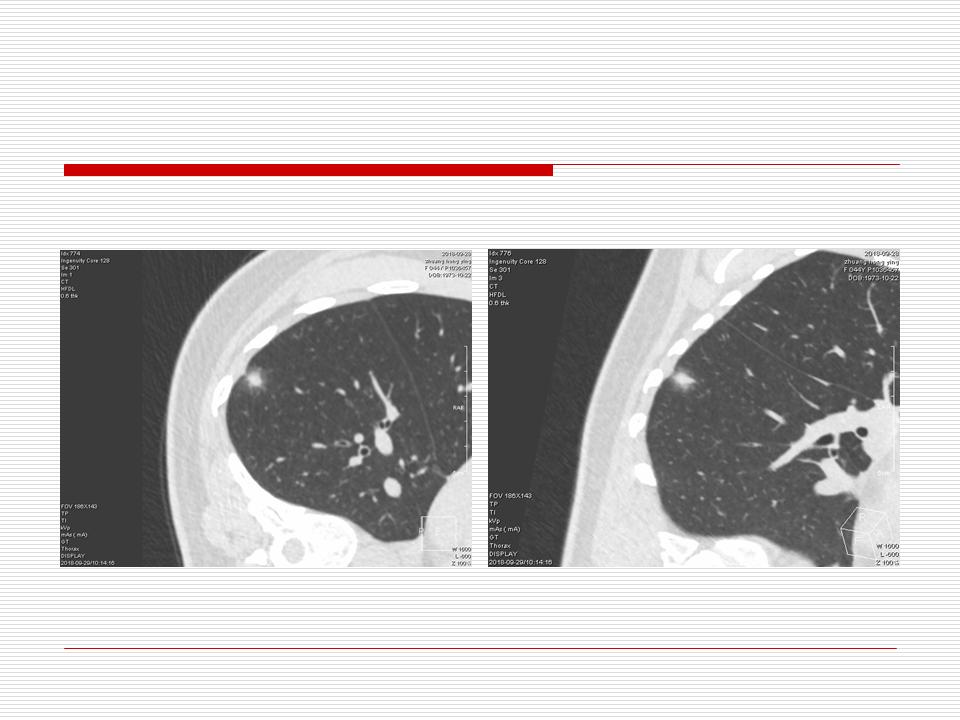

肺部阴影永恒且最重需要鉴别的是:到底是炎症还是肿瘤?但临床的病例中的影像表现难以界定或有些肿瘤特征,同时又有些炎症特点是非常常见的情况。作为临床医生我们怎么去总结分析,并找到之所以是炎症或之所以是肿瘤的细微差别或特点非常重要,也非常有用。2019.12.7浙江省2019年胸心外科学学术年会在宁波召开时,我的临床病例分析与经验总结<那些像肺癌的炎症与像炎症的肺癌>获得在大会交流的机会,以下为该PPT的内容,与你分享,希望对同道有益,有借鉴与启迪。若有探讨与进一不完善的建议,欢迎文末留言讨论: